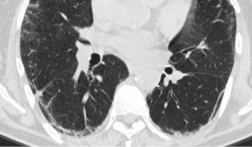

КТ имеет высокую чувствительность в выявлении изменений в легких, характерных для COVID-19. Применение КТ целесообразно для первичной оценки состояния ОГК у пациентов с тяжелыми прогрессирующими формами заболевания, а также для дифференциальной диагностики выявленных изменений и оценки динамики процесса. КТ позволяет выявить характерные изменения в легких у пациентов с COVID-19 еще до появления положительных лабораторных тестов на инфекцию с помощью МАНК. В то же время, КТ выявляет изменения легких у значительного числа пациентов с бессимптомной и легкой формами заболевания, которым не требуется госпитализация. Результаты КТ в этих случаях не влияют на тактику лечения и прогноз заболевания при наличии лабораторного подтверждения COVID-19. Поэтому массовое применение КТ для скрининга асимптомных и легких форм болезни не рекомендуется.

3. Применение лучевых методов у пациентов с симптомами ОРВИ легкой степени тяжести и стабильном состоянии пациента, возможно только по конкретным клиническим показаниям, в том числе при наличии факторов риска, при условии достаточных технических и организационных возможностей. Методом выбора в этом случае является КТ легких по стандартному протоколу без внутривенного контрастирования или РГ при ограниченной доступности КТ. Использование УЗИ в этих случаях нецелесообразно. Применение КТ исследования в сроки ранее 3 - 5 дней с момента появления симптомов заболевания является нецелесообразным.

4. Все выявляемые при лучевых исследованиях признаки, включая КТ-симптомы, не являются специфичными для какого-либо вида инфекции и не позволяют установить этиологический диагноз. Вне клинической (эпидемической) ситуации они не позволяют отнести выявленные изменения к пневмонии COVID-19 и дифференцировать их с другими пневмониями и невоспалительными заболеваниями. Данные лучевого исследования не заменяют результаты обследования на РНК SARS-CoV-2. Отсутствие изменений при КТ не исключают наличие COVID-19 и возможность развития пневмонии после проведения исследования.